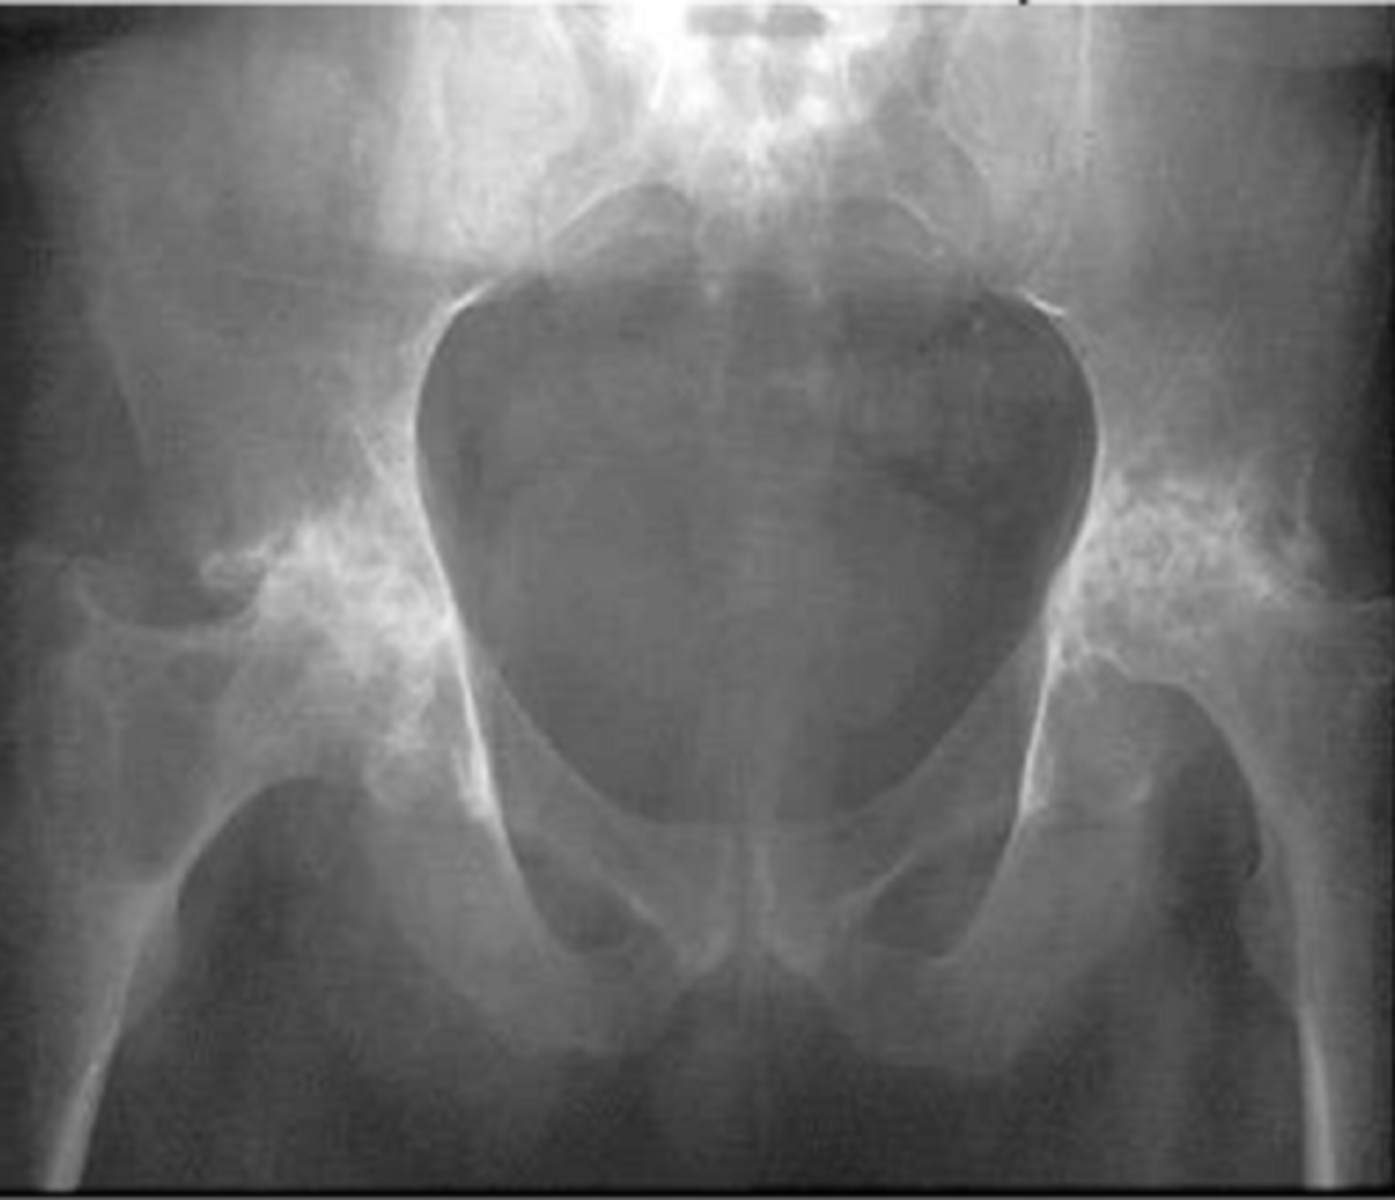

pelvic fractures

generally result from a high force injury (ex. MVA) accompanies by multiple internal trauma

STRUCTURE--> pelvic ring with generally more than one site

FUNCTIONAL DEFICITS--> pain with ambulation or inability to ambulate

COMPENSATORY MOVEMENTS--> slow antalgic, may need assistive device, may require fixation of the fracture sites

open book fracture of pelvis

disruption of pubic symphysis

*type of pelvic fracture